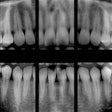

X-Ray: Page 7